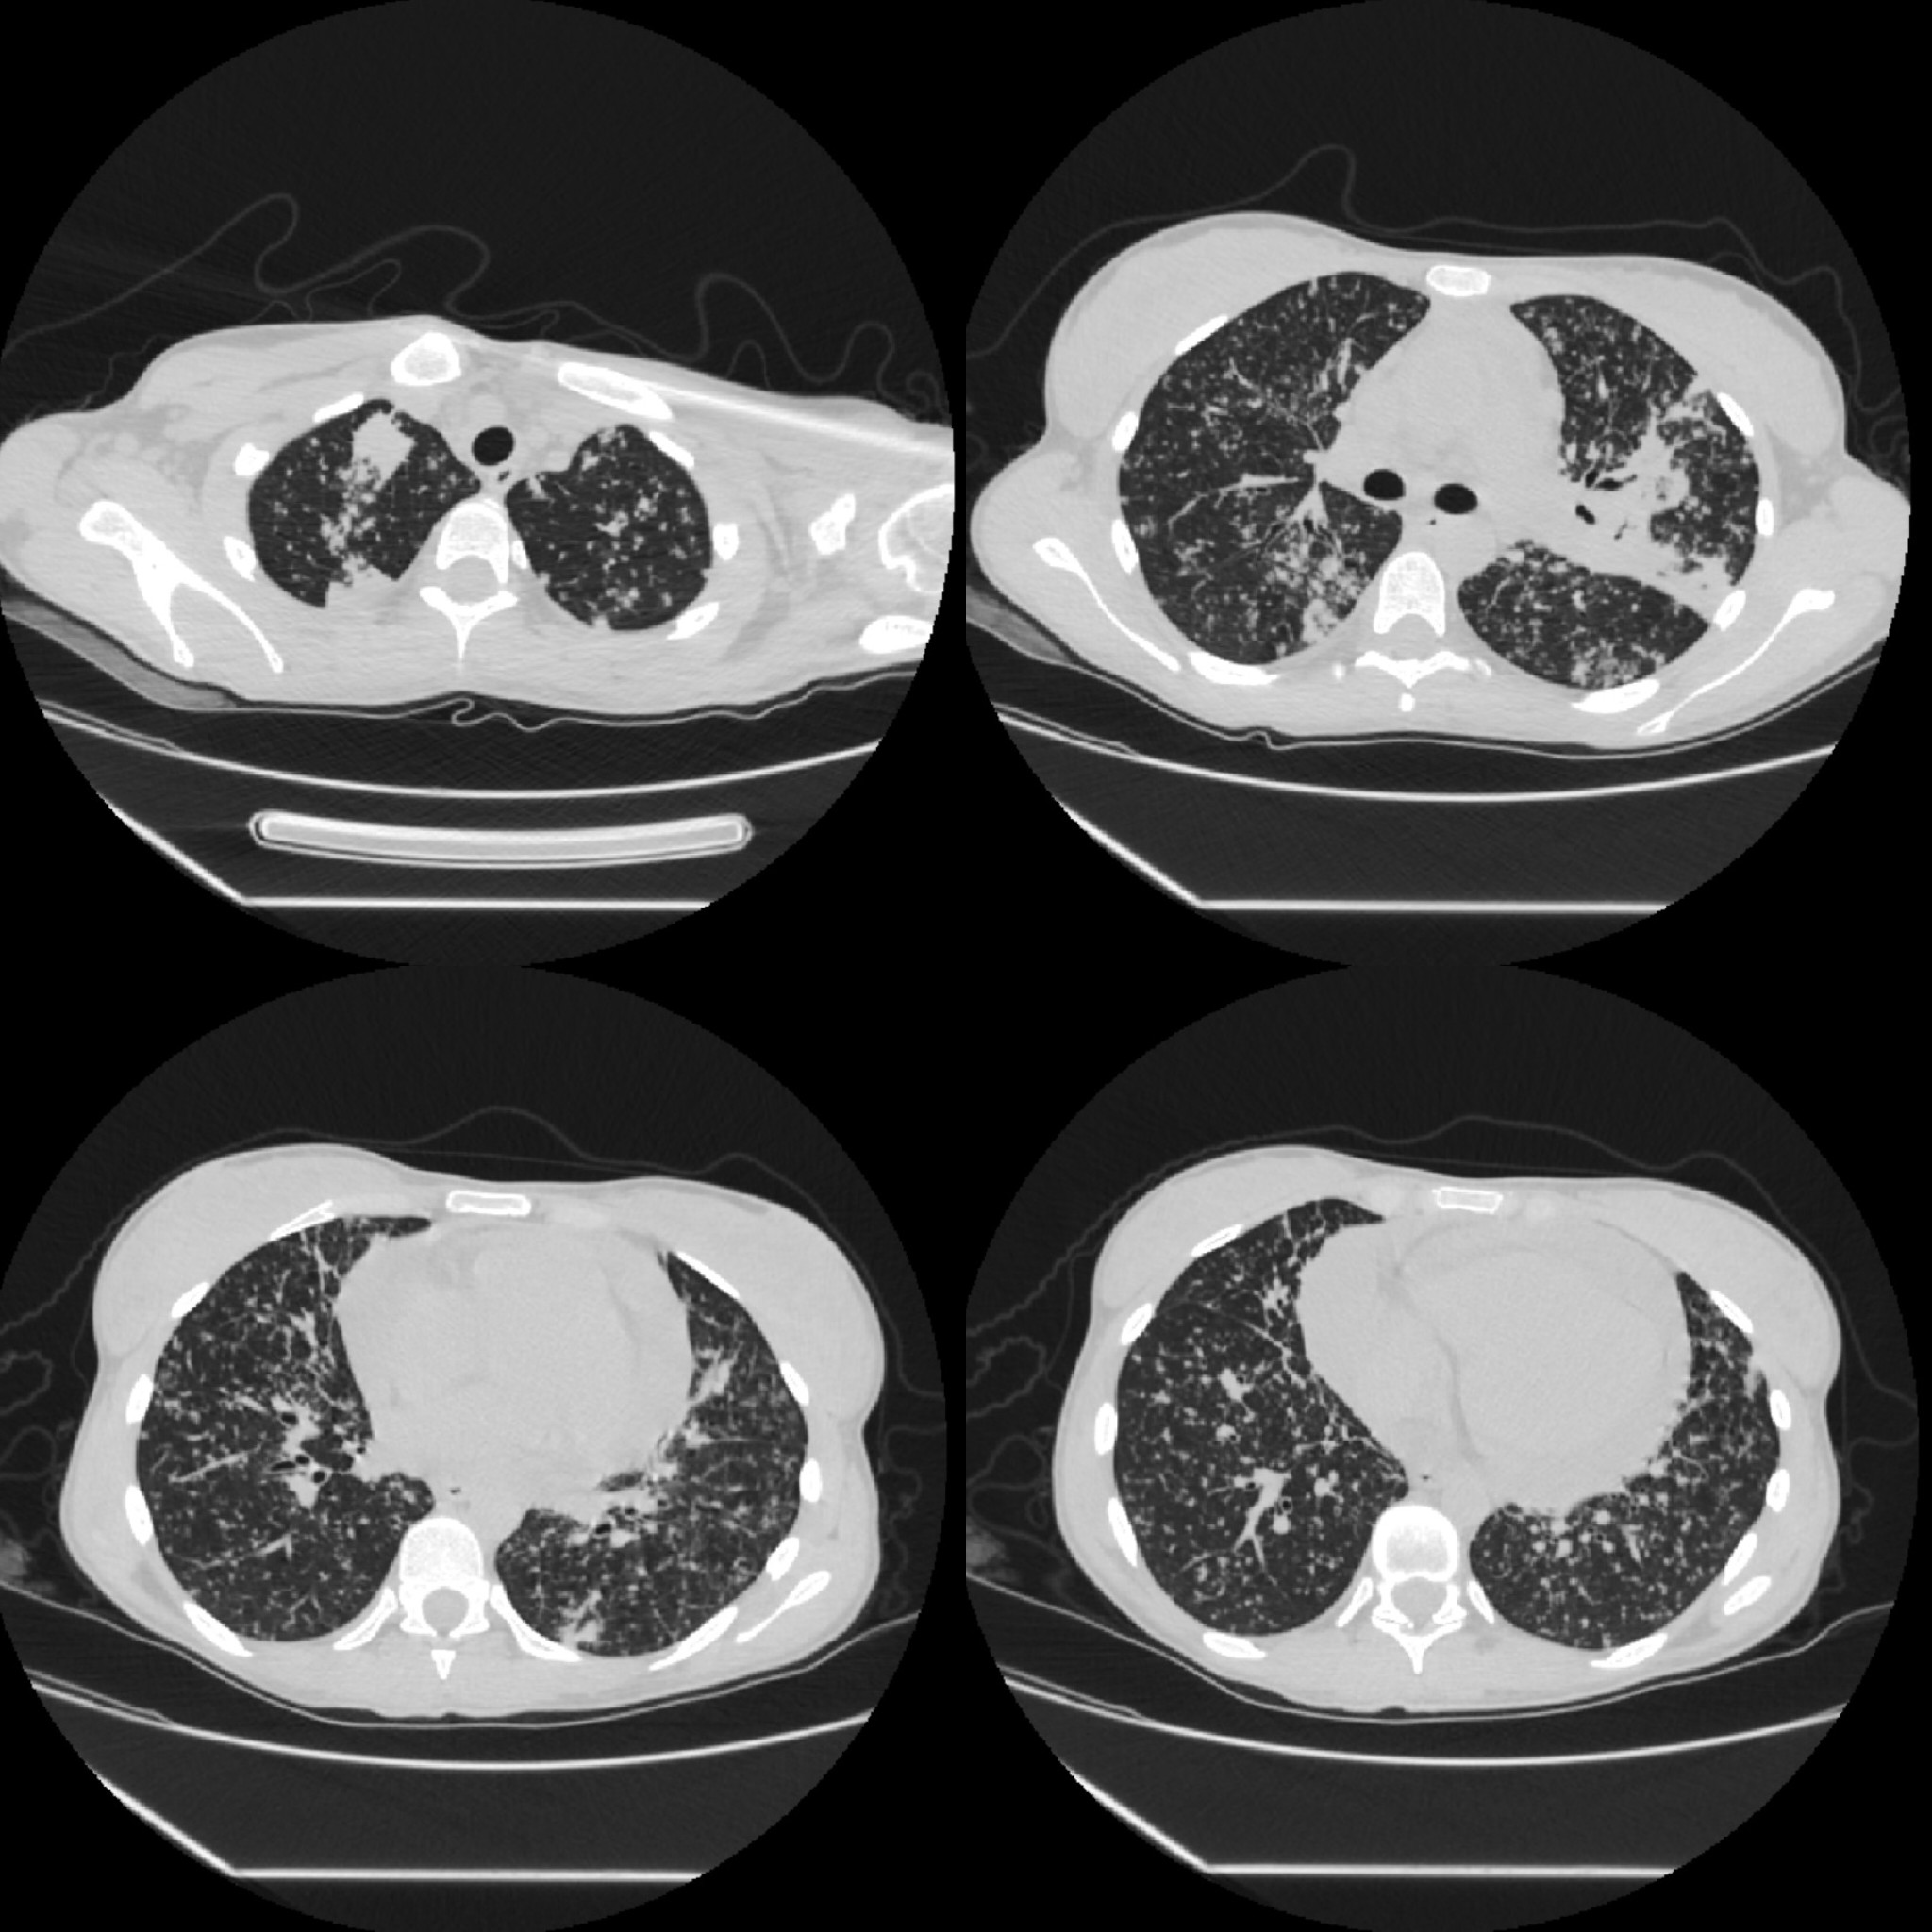

Non-contrast chest CT demonstrated diffuse miliary nodularity with focal consolidations in the right upper lobe segment S1 and left upper lobe segment S1, accompanied by hilar and mediastinal lymphadenopathy and a large pericardial effusion measuring up to 4 cm in thickness (Figures 2 and 3). A cardiology consultation was obtained. Screening transthoracic echocardiography (TTE) demonstrated a pericardial effusion measuring 3.8 cm, with evidence of cardiac tamponade. Although the patient remained hemodynamically stable, the large pericardial effusion with echocardiographic tamponade physiology warranted urgent echocardiography-guided pericardiocentesis to prevent progression to obstructive shock. The procedure reduced the effusion to 2.0 cm with resolution of tamponade, and a pericardial drain was left in situ. Pericardial fluid, sputum, urine, and stool samples were collected and tested for Mycobacterium tuberculosis (MTB) using smear microscopy, the Xpert MTB/RIF assay, and culture. MTB was detected by the Xpert MTB/RIF assay (positive for MTB DNA without rifampicin resistance) in multiple specimens, including sputum, pericardial fluid, and feces. Smear microscopy was negative in all samples except for scant acid-fast bacilli (AFB) detected in a single sputum specimen (Table 1).

Figure 2. Non-contrast chest CT scan, lung window (description above in the text).